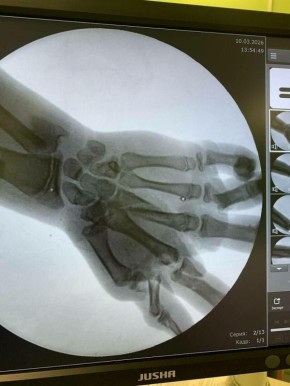

ЧП случилось в Калининграде – во дворе частного дома. Ребенка экстренно госпитализировали. Врачи Детской областной больницы смогли сохранить ребенку кисть, проведя две сложных, ювелирно точных операции с разницей в несколько суток.

Также мальчику диагностировали перелом нижней трети левого предплечья со смещением, раны левой голени и лба.

Фото: правительство калининградской области